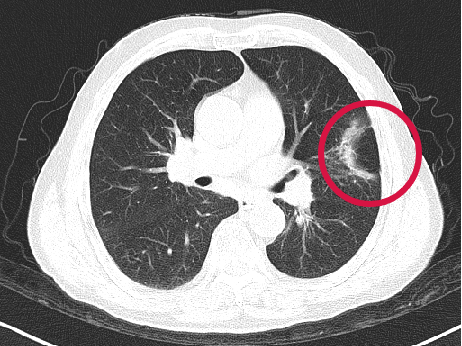

術(shù)前圖像

▲患者因體檢發(fā)現(xiàn)左肺上葉舌段結(jié)節(jié),考慮周圍型肺癌可能。因高齡、肺氣腫無法手術(shù),遂來院接受肺結(jié)節(jié)冷凍消融治療,術(shù)后病理為肺癌,定期隨訪提示腫瘤逐漸縮小。